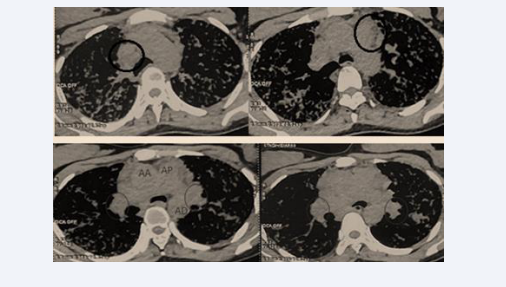

The mediastinal window demonstrated large bilateral hilar and mediastinal lymphadenopathies (Figure 4).

Figure 4 Large bilateral hilar and mediastinal lymphadenopathies.

Figure 4: Large bilateral hilar and mediastinal lymphadenopathies.

After two months of corticosteroid therapy, the patient showed significant improvement, with reduced dyspnea, disappearance of cough and anxiety, resolution of crackles, and a weight gain of 15 kg. At six months, dyspnea and crackles had completely disappeared, and the patient resumed her daily activities, including work. ACE levels showed a significant decrease (96 U/L vs. 192 U/L), and the six-minute walk test revealed normal oxygen saturation in ambient air (SpO? = 99%) after walking 280 meters without dyspnea. Follow-up chest CT showed a marked regression of nodules, micronodules, and hilar and mediastinal lymphadenopathy (Figure 5).

Figure 5 Follow-up chest CT showing significant regression of nodules, micronodules, and hilar and mediastinal lymphadenopathy.

Figure 5: Follow-up chest CT showing significant regression of nodules, micronodules, and hilar and mediastinal lymphadenopathy.